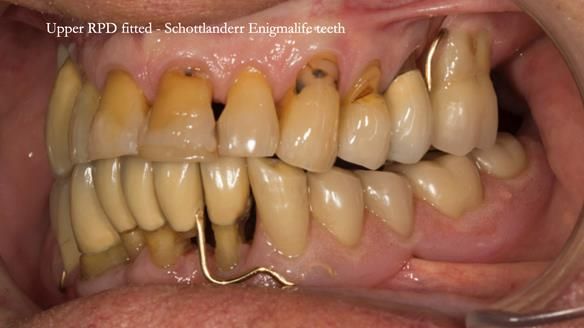

This case was always about function, not aesthetics.

Ken’s teeth were never going to look perfect.

There were stained composites, old restorations, and obvious wear.

That was accepted from the outset.

The way Rowan lengthened the teeth — particularly in the upper RPD — to match the existing gingival recession on the remaining teeth was superb. The dentures sit naturally within the context of the rest of the mouth.